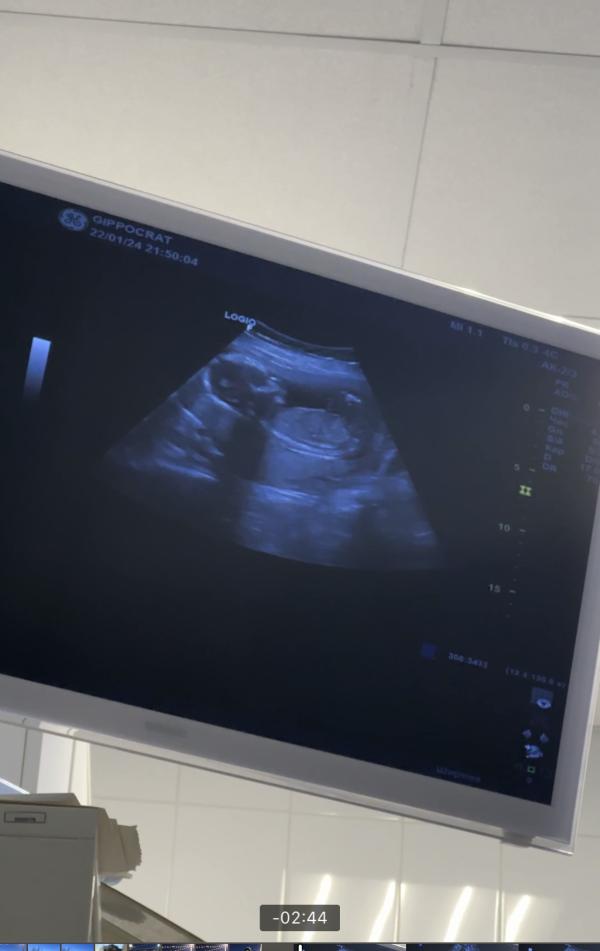

У нас будет сыночек 👶

Вчера пошла на узи, потому что несколько дней потягивало живот, какая то тяжесть была… в итоге все в норме, либо матка тянется, либо реакция из за изменения дозы утрожестана в меньшую сторону) сразу и узнала что то там прячется))) сразу начал активничать, ручкой помахал 🥹